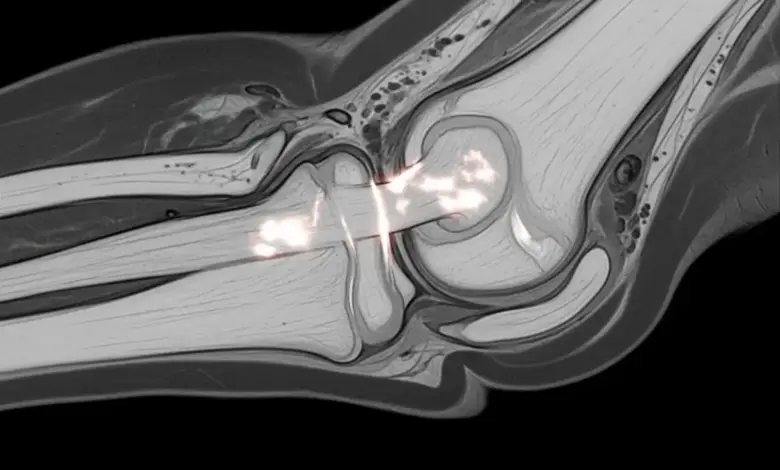

- Ressonância magnética é o exame mais útil quando existe dúvida diagnóstica ou suspeita de lesão mais complexa.

Qual exame mostra melhor a lesão do ligamento colateral medial?